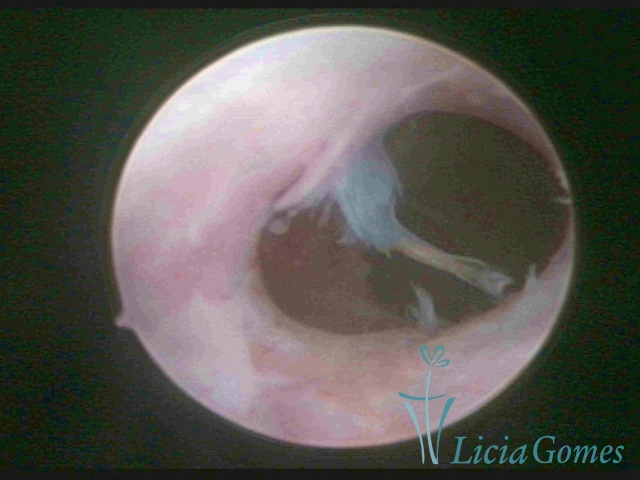

• SINÉQUIA TIPO FIBROMUSCULAR

As Sinéquia uterinas são cicatrizes (aderências) entre as superfícies das paredes uterinas, que podem ocorrer após manipulação cirúrgica, ou curetagem uterina, ou após um processo inflamatório na cavidade uterina (endometrite), podendo levar a alterações menstruais, infertilidade, e complicações obstétricas, como abortamento, parto prematuro.